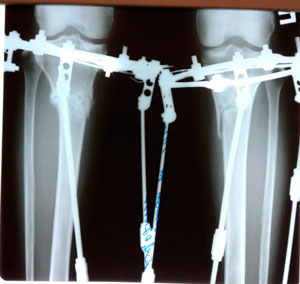

Ровные ножжки!

Re: Ровные ножжки!

Дата операции - 12.04.2019г

Дата снятия аппаратов - 25.07.2019.

Срок сращения- 103 дня.